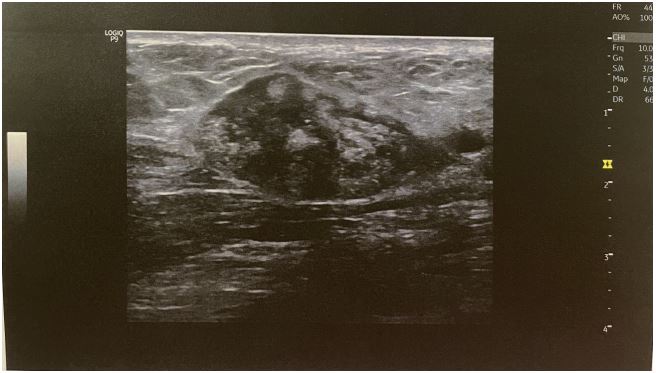

A 45-year-old Caucasian female attended our outpatient clinic during her annual follow-up, with a painless, palpable mass in the upper outer quadrant of her left breast. She denied family history with breast or gynecological malignancies and had never received hormonal therapy or other medication. A clinical examination revealed a painless palpable mobile lump in the aforementioned area at a distance of approximately 10 cm from the nipple. There was no axillary or supraclavicular lymphadenopathy. The other breast was into normal appearance and consistency. The lesion had incidentally been found two years previous to this during her annual mammogram and was originally considered to be fibroadenoma. That ultrasound had detected a hypoechoic oval shape nodule, with no detectable Doppler flow, located in the upper outer quadrant of the left breast, measuring 2.6 cm (Figure 1). The follow-up mammogram detected an enlarged, dense, well-circumscribed oval lesion with no calcifications inside or around, without lymphadenopathy (Figure 2). The lump was classified as category 4 according to BIRADS (Breast ImagingReporting and Data System) criteria. Based on clinical and imaging findings, a Tru Cut biopsy through U/S was then conducted. The resulting pathology revealed spindle cells with elongated cigar-shaped nuclei and eosinophilic cytoplasm (H+E stain x 20) (Figure 3). Despite the benign nature of the tumor, the patient was offered the option of surgical removal of the lump in order to avoid diagnostic dilemmas and pitfalls. A consent form was signed and under general anesthesia the lesion was resected in macroscopic clear margins leaving a drain in place. Postoperative course was without noteworthy incidence and the patient was discharged the hospital the next day. The pathology of the specimen showed intersecting fascicles of elongated smooth muscle cells with no atypia or mitotic activity. Immunohistochemistry depicted strong expression of desmin, a characteristic of smooth muscle neoplasms, which confirmed the diagnosis of leiomyoma, while the absence of p63 marker excluded metaplastic carcinoma (Figures 4,5). Two years after the operation the patient has no symptoms and the mammogram shows no evidence of recurrence.

Figure 1: Solid Mass with heterogeneous morphology without vascularization in Doppler image.